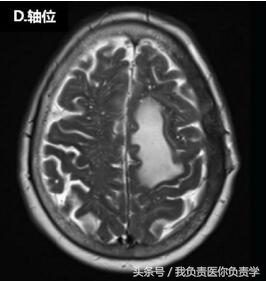

脑MRI显示,患者左侧额-顶部有一较大占位,增强扫描可见强化,从颅内、外延伸至上矢状窦(如图下所示),累及左侧额叶、顶叶和颞骨,左侧硬脑膜增厚。在颅内肿块压迫下,临近部位脑组织表现出血管性水肿。

▲头皮下占位病变。上图可见一较大的颅内外占位性病变,延伸至上矢状窦、大脑、软组织和颅骨。图(A)和图(B)T1增强见左侧硬脑膜增厚;图(C)T1可见脑水肿,图(D)为T2。